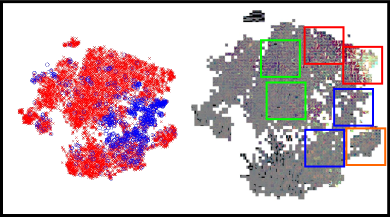

CNNs can be interpreted as models that transform the input images into a feature representation in which classes can be separated by the linear model in the last layer. The topology of such a space will depend on the ability of the deep learning features to characterize the inputs. Hence, if features are sufficiently good to differentiate each type of input, at least two well separated regions would be visually identified. Due to the high dimensionality of the feature space, a method is needed to embed multidimensional vectors in a 2D space, while preserving the pairwise distances of the points. The -distributed stochastic neighbor embedding (-SNE) was recently introduced for this purpose (Van Der Maaten, 2014). We followed this approach to study the complementarity of each characterization method, and to qualitatively assess how their integration contribute to improve their original discrimination ability. Figure 14 presents the -SNE mappings of the DIARETDB1 test samples for each characterization approach and for our combined feature vector. The CNN descriptors corresponds to those learned in Experiment 1. The figure also includes a visual representation of the organization of the patches in the embedding space. In general, it is possible to see that the ensemble approach groups the majority of the true positive candidates within a single neighboring area. By contrast, the individual characterization strategies are not able to achieve a single cluster but rather obtain two–in the case of the deep learned features–or more–using the hand crafted features.

Detailed regions of the embeddings are depicted in Figure 15. This allows better visualization of particular scenarios such as the patches around the true red lesions, the false positive candidates located in the vascular structures, the artifacts due to speckles of dirt in the lens–which are typical of the images in DIARETDB1–and the false detections within the optic disc. In general, it is possible to observe that CNN features are able to better characterize the orientation and the visual appearance of the true lesion candidates, while the hand crafted features can detect the less obvious lesions under low contrast conditions. The ability of the CNN features to discriminate orientations are more evident when dealing with vascular structures. The hand crafted approach, by contrast, is only able to capture the overall size of the vessels and their intensity properties. When combining both strategies, the main advantages of each of them are maintained. The robustness against artifacts is evident for both the deep learning based and the hand crafted features, as these false positive candidates are grouped together into separate clusters from the true lesions. A similar behavior is observed when dealing with false candidates within the optic disc area.

In general, the integration of both the deep learned and the hand crafted features significantly improved results compared to using either approach separately. In a per lesion evaluation, the combined approach achieved a consistently higher CPM value both in the e-ophtha and DIARETDB1 test sets, and also a higher per lesion sensitivity for FPI=1, which corresponds to a clinically relevant number of false positives (Niemeijer et al., 2010). These values are also higher than those obtained by two recently published baseline methods that were evaluated on the same data set. A similar behavior is observed when evaluating the method on a per image basis. The combined approach improved the performance obtained by each characterization approach separately, meaning that the integration of both sources of information obtains a better characterization of the lesion candidates and, consequently, a more accurate detection of the individual lesions. This is supported by the extensive analysis presented in Section 4.3. Despite the fact that sufficiently deep CNNs are known to be able to learn any function of arbitrary complexity, the lack of data with lesion-level annotations does not allow our network to identify the same properties that the hand crafted features do. Nevertheless, in the analysis of the -SNE mapping presented for each method (Figures 14 and 15) it is possible to see that the CNN has the ability to characterize fine-grained details such as the orientation of the lesion that are ignored by the manually selected descriptors. On the other hand, the hand crafted features have the ability to discriminate other low contrast lesions (Figure 15), specially hemorrhages (Figure 8(b)). As a result, the ensemble approach is able to outperform each individual alternative, improving performance for detecting both MA and HE simultaneously. Due to the high cost of accurately annotating small lesions, we hypothesize that this observation will continue to stand in the near future.